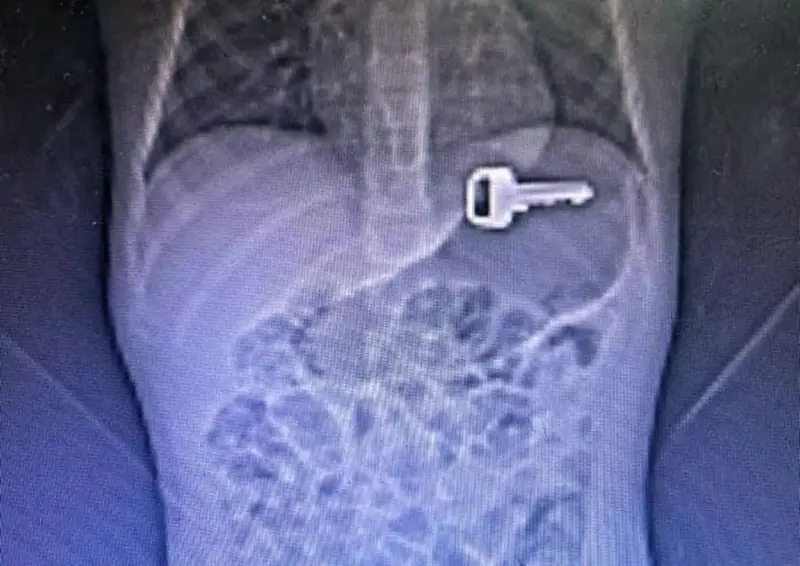

Dentre os procedimentos mais requisitados, destacam-se as análises clínicas, que totalizaram 720.323 exames, seguidas por radiografias (36.956), hemodiálises (23.024), ultrassonografias eletivas (17.995), tomografias computadorizadas eletivas (10.269), diagnósticos histopatológicos (6.478) e outros exames (27.799).